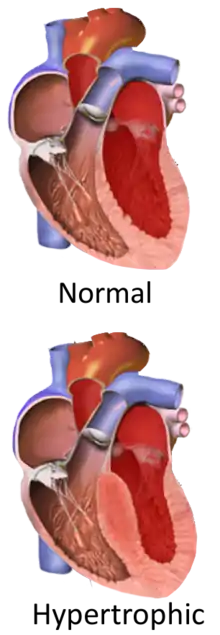

Hypertrophic cardiomyopathy (HCM, or HOCM when obstructive) is a condition in which muscle tissues of the heart become thickened without an obvious cause.[8] The parts of the heart most commonly affected are the interventricular septum and the ventricles.[10] This results in the heart being less able to pump blood effectively and also may cause electrical conduction problems.[3] Specifically, within the bundle branches that conduct impulses through the interventricular septum and into the Purkinje fibers, as these are responsible for the depolarization of contractile cells of both ventricles.[11]

Pathophysiology

Ventricular hypertrophy causes a dynamic pressure gradient across the left ventricular outflow tract (LVOT), which is associated with further narrowing of the outflow during systole. Pulling of the mitral valve leaflets towards the septum contributes to the outflow obstruction. This pulling is though to occur by several proposed mechanisms, including that flow of blood through the narrowed outflow tract results in it having a higher velocity, and less pressure through the Venturi effect.[17] This low pressure then causes the anterior leaflet of the mitral valve to be pulled into the outflow tract, resulting in further obstruction.[32]

Depending on whether the distortion of normal heart anatomy causes an obstruction of the outflow of blood from the left ventricle of the heart, HCM can be classified as obstructive or non-obstructive.[35] The obstructive variant of HCM is hypertrophic obstructive cardiomyopathy (HOCM), also historically known as idiopathic hypertrophic subaortic stenosis (IHSS) or asymmetric septal hypertrophy (ASH).[36] The diagnosis of left ventricular outflow tract obstruction is usually made by echocardiographic assessment and is defined as a peak left ventricular outflow tract gradient of ≥ 30 mmHg.[37]